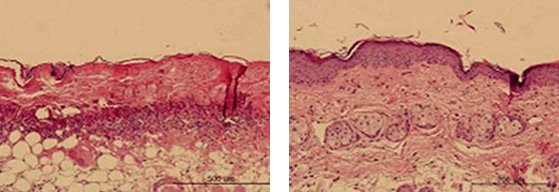

These slides show the changes in dermatitis associated inflammatory cells following 830 nm LED irradiation in a rat model: A marked reduction in inflammatory infiltration can be seen.1

1 Is light-emitting diode phototherapy (LED-LLLT) really effective?